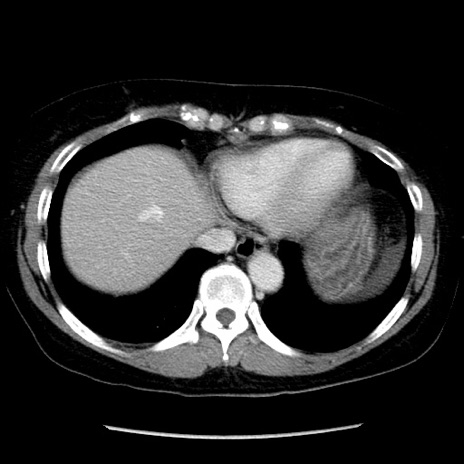

症例6(横断像)

【症例】50歳代女性

【主訴】下腹部痛

【現病歴】本日朝より下痢2回あり。 昼食を食べた後、嘔吐3回、下腹部痛認め、症状軽快せず、当院救急搬送。

最終食事:本日昼(生ものなし)。 昨日の夜、刺身を食ぺたとのこと。周囲に同様の症状の者なし。普段、排便は毎日あるとのこと。

【既往歴】卵巣癌術後(8年前に当院で卵巣摘出)

【身体所見】 意識清明、腹部:平坦、腸蠕動音→、やや硬、下腹部自発痛・圧痛あり、反跳痛あり、筋性防御なし。

【データ】WBC 16000、CRP 0.01